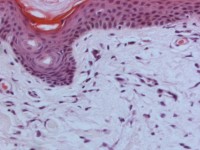

Diagnostiek: PA lesionale huid (formaline). Histopathologisch

vertonen de papillaire lesies een focale depositie van mucine in de dermis.

Er is ook een toename van het aantal fibroblasten en van het collageen. Plasmacel

infiltraten kunnen worden gezien en de collageenvezels zijn vaak verdikt. Kleuring

met Alcian-Blue (slijmkleuring) voor aantonen van mucine deposities. Laboratoriumonderzoek

![Scleromyxoedeem (lichen myxoedematosus) (click on photo to enlarge) [source: www.huidziekten.nl] Scleromyxoedeem (lichen myxoedematosus)](../../../images/lichen-myxoedematosus-13z.jpg) |

| PA mucinosis

papulosa |